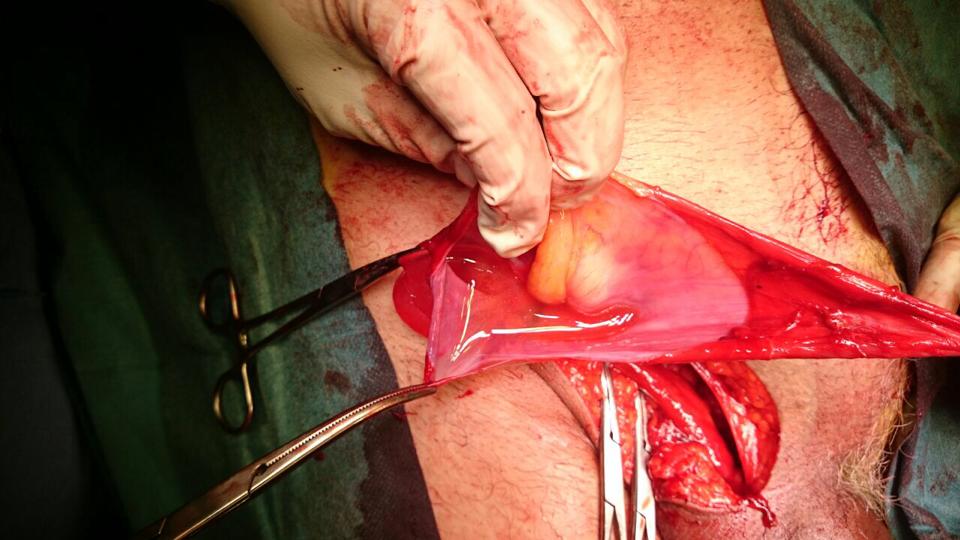

Complicated SSTIs can also be labeled as non-necrotizing or necrotizing infections. Necrotizing infections maximum typically contain the muscular fascial layers but may additionally contain the dermal, subcutaneous, and muscle layers and warrant activated, competitive surgical debridement.

Necrotizing SSTIs (cellulitis, fasciitis, myositis, Fournier’s gangrene) require surgical intervention which includes drainage and debridement of necrotic tissue further to antibiotic remedy.